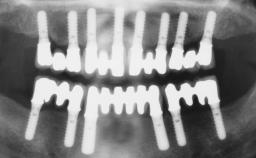

Immediate Loading of Six Implants in the Mandible and Six Implants in the Maxilla and Final Restoration with Full-Arch CAD/CAM Metal Framework FDPs Involving Digital Planning and Guided Surgery

# of Implants 12

Guided Surgery Yes

Defining Characteristics Fully edentulous upper jaw to be rehabilitated with four or more implants

Modality 6+ implants with immediate loading